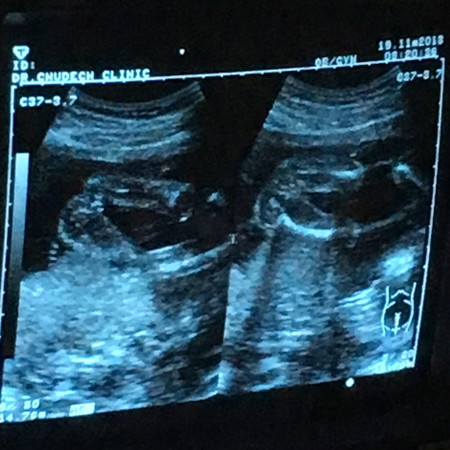

เพศลูก

แบบนี้น้องเป็นผู้หญิงใช่มั้ยคะ แม่ ๆ ช่วยดูหน่อยค่ะ

น่าจะผญ.นะคะแม่ แล้วหมอว่าไงบ่างค่ะ

น่าจะลุกสาวนะคะ

ดูไม่ออกเลยค่ะ

น่าจะหญิงคะ

ผู้ชายไหมคะ